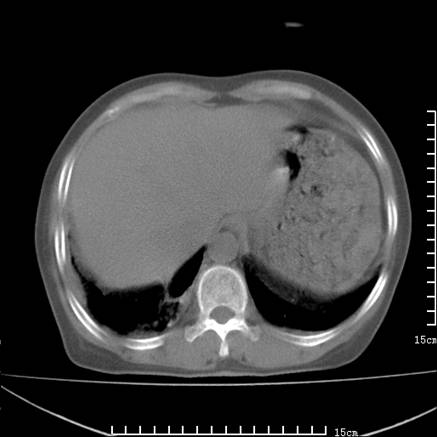

女,王某,58岁,咳嗽三个月余,基层医院二个月前诊为肺结核,用抗结核药二个月无明显疗效。

心包积液致肺瘀血.右侧周围型肺癌伴肺内转移,中间裂积液,叶间胸膜肥厚.右上肺大泡,右侧胸膜肥厚.

双肺继发型tb,心功能不全并肺淤血、心包、双侧叶间裂积液,肺大泡,右下胸膜肥厚钙化。